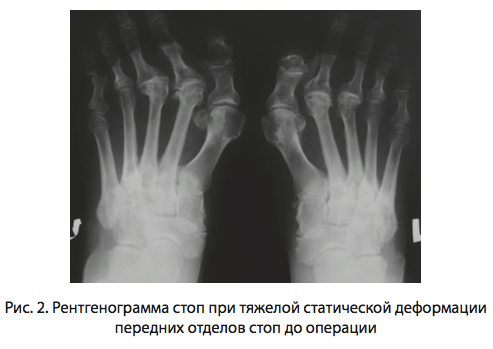

Комплекс деформаций переднего отдела стоп (фиг. 1) поражает трудоспособное население, ухудшает качество жизни пациентов, ограничивая повседневную активность и затрудняя подбор обуви [1, 2]. Многообразие методов хирургического лечения комбинированного плоскостопия дает возможность выбора наиболее эффективных вариантов с минимальным количеством осложнений и рецидивов [2, 4]. В анатомо-физиологических особенностях стопы, таких, как многократная повседневная нагрузка на сегмент, малый объем компартмента и высокая уязвимость суставов особенно важным является принцип сохранения головки плюсневой кости с целью физиологической функции всего плюсне-фалангового сустава, при проведении хирургического лечения [5, 6]. Ригидный вывих малого пальца является одним из наиболее частых компонентов комбинированного плоскостопия (фиг. 2), как следствие выраженной деформации переднего отдела стоп, причем консервативные методы лечения неэффективны [5, 7]. Оперативное восстановление функции плюсне-фалангового сустава и поперечного свода стопы, таким образом, становится отправной точкой в комплексе лечения поперечного плоскостопия [7].

В зависимости от набора деформаций переднего отдела стоп проведены операции, диафизарная остеотомия Scarf первой плюсневой кости и операции Akin на основной фаланге 1 пальца для дополнения коррекции деформации первого луча стопы. Ригидные вывихи 2, 3, 4, 5 пальцев лечили сегментарной резекцией диафиза плюсневой кости с использованием метода Short Beam (фиг. 3) (SB) (Патент РФ No 2576790 от 10.02.2016).